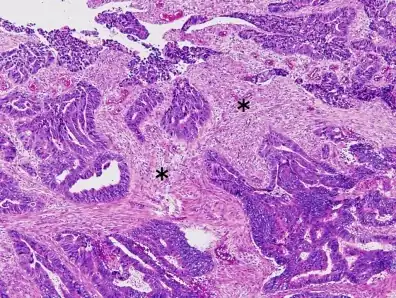

-

Colorectal carcinoma with desmoplastic reaction (*) -

Dirty necrosis

- Frequently desmoplasia

- Dirty necrosis, consisting of extensive central necrosis with granular eosinophilic karyorrhectic cell detritus.[6][7] It is located within the glandular lumina,[7] or often with a garland of cribriform glands in their vicinity.[6]